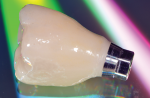

These difficulties can be overcome by using a screw-retained crown that offers an angulated screw channel (eg, the authors use the NobelProcera Full-Contour Zirconia Implant Crown; nobelbiocare.com) (Figure 7). The technology has allowed clinicians to overcome access issues by re-angulating the screw channel up to 25 degrees, thereby creating screw-retained restorations with favorable esthetics and ease of delivery in the posterior.

Coupled with this technology is the ability to mill the restoration from a highly esthetic, full-contour monolithic zirconia material that fulfills all of the functional and esthetic requirements of a posterior molar site (Figure 8 through Figure 10).